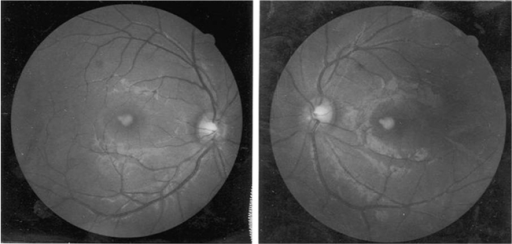

- 9방향 주시검사: 내전 시 상전 제한